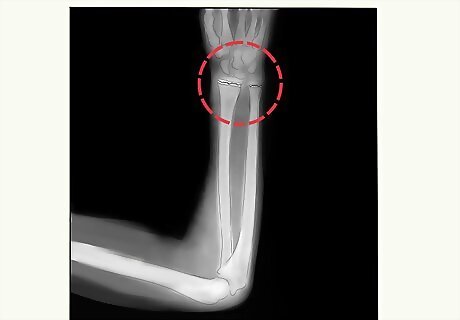

Get imaging tests. In addition to your exam, your doctor may order imaging tests. X-rays or an MRI can give the doctor a better idea of the fracture. They can also help determine the best treatment for you.

Have your fracture fixed. Following your exam and an X-ray or MRI, your doctor will let you know if you have a growth plate fracture. The treatment to fix the fracture will depend on its severity. Fractures that are less severe may need a cast or splint. You may require surgery for more serious fractures. Each treatment helps the growth plate and bone heal properly. This can prevent permanent damage or deformity. Your doctor may set the plate and bone in a cast or splint if your break isn’t severe. You may need surgery if the break is unstable or your bone fragments are displaced. Surgery generally sets the bones in place with screws, wires, or metal plates.